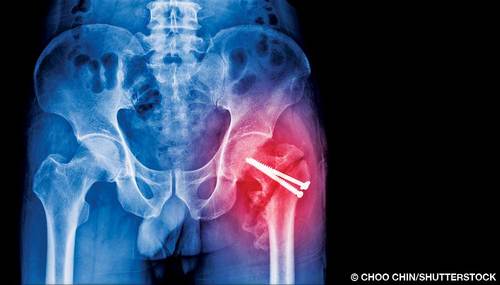

I suffered a hip fracture and three weeks ago had surgery to insert a plate and screws on the neck of my femur. Is it safe to dive eight weeks after surgery, and is there a risk of decompression illness (DCI) or osteonecrosis?

A: While you should seek a specific answer from a local physician trained in dive medicine, I can offer general guidelines. The industry standard for a return to diving after any fracture is for your doctor to release you for full and unrestricted activity, including contact sports, and then have an additional convalescent period of one-half the length of the regular healing time for the fracture. This extra time is to recover any lost physical fitness and aerobic capacity due to atrophy during the healing and rehabilitation process. If your doctor releases you for full and unrestricted activity after six weeks, for example, you should add three weeks for a total waiting period of nine weeks. These numbers are merely an example, and you should consult with your treating physician for a definitive answer.

The ability to conduct rigorous exercise, stress that joint through the range expected, and have a full recovery without restrictions, risk of injury, dislocation or other problems are issues to discuss with your surgeon.

Osteonecrosis is more closely related to long-term exposure without following the proper decompression protocols and is of very little concern in your case. There are very few documented cases of dysbaric osteonecrosis (DON) in recreational divers. Data suggest that scar tissue doesn't ongas and offgas as efficiently as healthy tissue; however, diving well within recreational limits can mitigate, although not eliminate, risk of DCI.